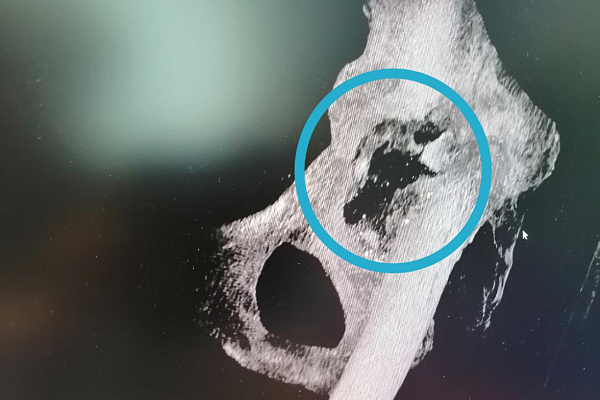

"Получили удовольствие от работы" - так оценивают первый опыт установки индивидуального имплантата травматологи-ортопеды Андрей Миронов и Евгений Бойко. Они совместно оперировали 70-летнюю пациентку с тяжелым дефектом тазовой кости. Стандартным эндопротезированием тазобедренного сустава проблема не решалась. Лизис превратил вертлужную впадину в решето, разрушив костные структуры на довольно большой площади (фото). Поэтому фиксировать эндопротез было просто не к чему.

По КТ-снимкам 3D-принтер напечатал точную копию поврежденной тазовой кости. Затем был смоделирован фрагмент для замещения дефекта. Его выполнили в двух вариантах: из полимерного материала – для пробной примерки и из титана – для окончательной установки. Во время хирургического вмешательства 3D-эндопротез идеально встал на своё место. Заместив разрушенный участок кости титановым «двойником», травматологи-ортопеды смогли приступить к следующему этапу лечения – эндопротезированию всего тазобедренного сустава. Через сутки пациентка уже вставала на ноги с помощью дополнительной опоры, а сегодня под контролем инструкторов-методистов ЛФК разрабатывает новый сустав при ходьбе.